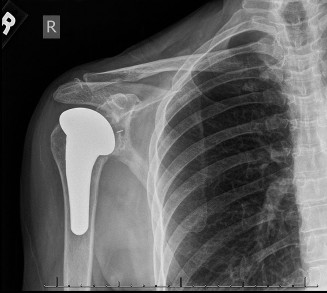

[Post-operative radiograph demonstrating well-fixed total shoulder arthroplasty components.]